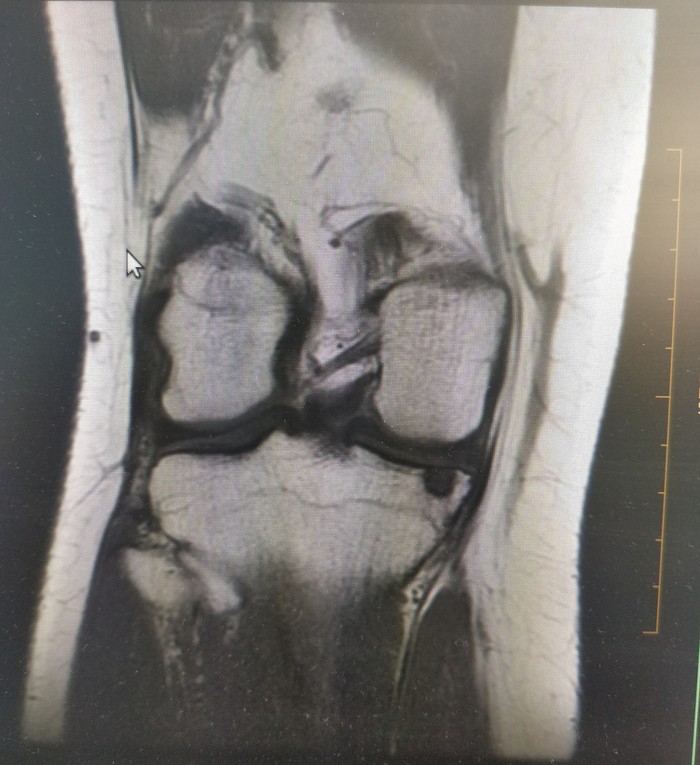

2. Часто получается такая дичь)

3. Колени в этой проекции всегда страусы.